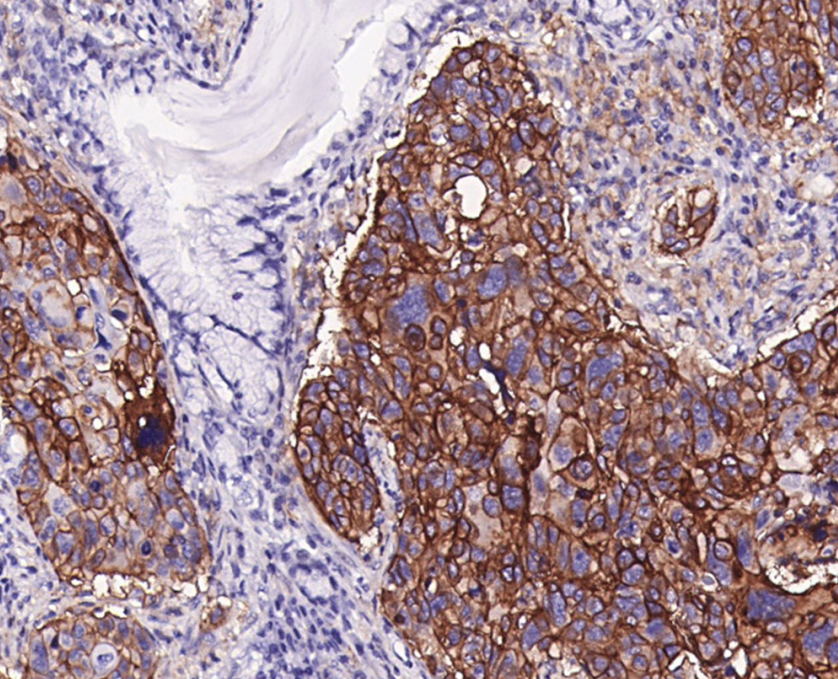

Clone number: SP142

isotype: rabbit monoclonal antibody

Cellular localization: cell membrane

Positive control: Placenta/Lung cancer

Programmed cell death ligand 1 (PD-L1), also known as CD274 or B7-H1, is a type I transmembrane protein involved in cellular regulation and immune responses.PD-L1 protein is widely expressed in antigen-presenting cells, activated T/B cells, macrophages, placental trophoblast cells, myocardial endothelial and thymic cortical epithelial cells.PD-L1 has been implicated in the immune escape mechanism of tumors, and PD-L1 protein expression was successively detected in human PD-L1 protein expression has been detected in breast, lung, gastric, intestinal, pancreatic and melanoma tumors. Studies have shown that PD-L1 expressed by tumor cells and antigen-presenting cells in the tumor microenvironment can inhibit the activation of tumor antigen-specific T cells via the PD-1/PD-L1 signaling pathway, and down-regulate the T cell-mediated immune response to tumors.

PD-L1 antibody reagents can specifically bind to PD-L1 molecular antigens. Immunohistochemical kits containing PD-L1 antibody reagents are suitable for evaluating the expression level of PD-L1 in tumors (such as non-small cell lung cancer and melanoma).